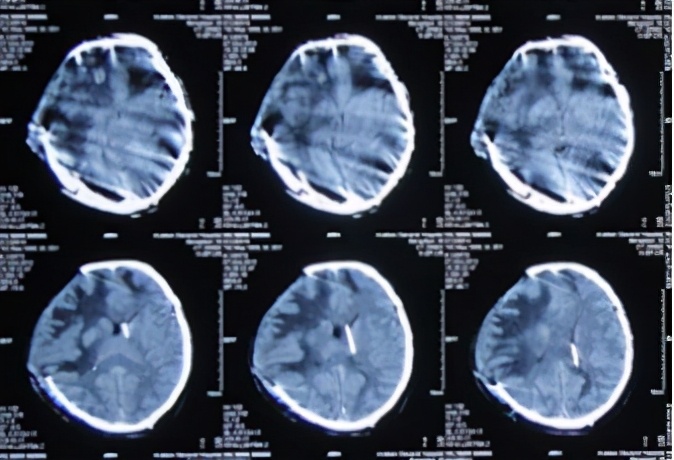

患者于2013年9月17日清晨因车祸致头部外伤、昏迷,急诊于山东省聊城市某医院就诊,头CT检查发现双额及右颞叶多发脑挫裂伤并右侧脑室受压、中线左移(图-1),当天进行了右侧额颞叶脑挫裂伤血肿清除并去骨瓣减压术,术后头CT:去骨瓣减压术后状态(图-2)。

图-1:2013年9月17日术前头CT

图-2:2013年9月17日术后头CT